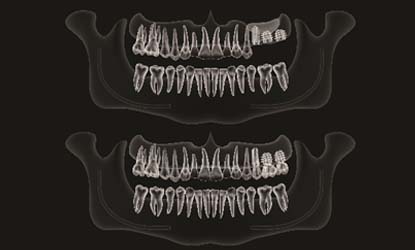

Problema: Nepakankamas kaulo aukštis dantų implantui

Tikslas:

Pakeisti trūkstamą dantį dantų implantu per vieną kartą

Rezultatas:

Atlikta sinuso elevacijos procedūra ir dėka gero pirminio stabilumo vienmomentiškai įsriegti dantų implantai